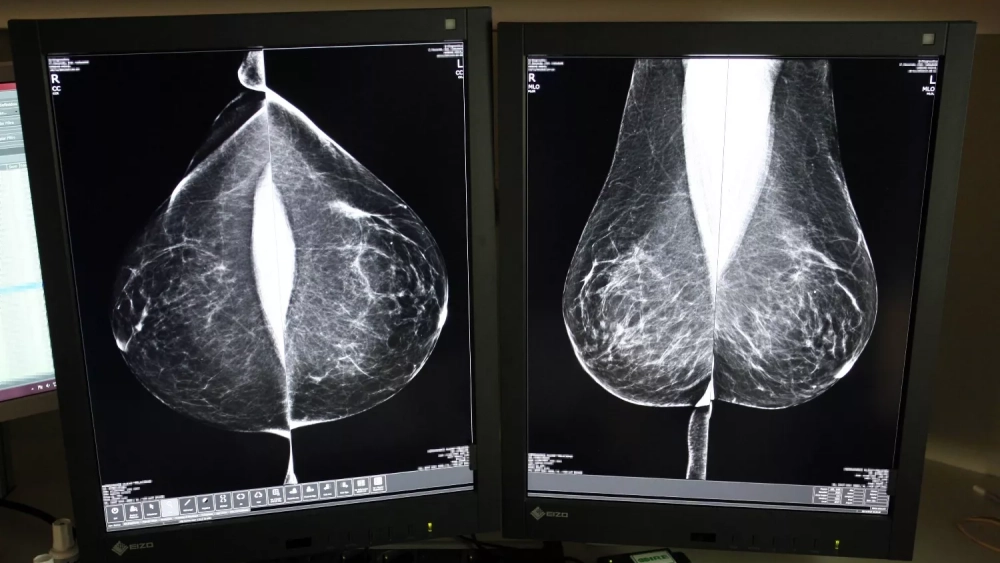

Desde su puesta en marcha en 1992, el programa se basa en el sistema de doble lectura, un protocolo que establece que cada mamografía sea evaluada por al menos dos radiólogos, de forma independiente, aumentando así la fiabilidad de los diagnósticos. Sin embargo, aumenta la carga de trabajo y plazos, motivo por el cual Sacyl ha optado, de nuevo, por externalizar el servicio al que el año pasado dedicó casi cuatro millones.

Servicio de Mamografía del Hospital Río Hortega de Valladolid